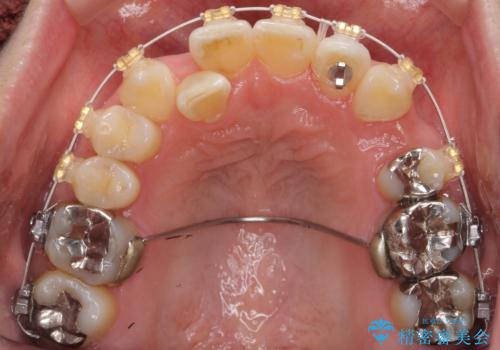

40代の矯正 八重歯を綺麗に

- 審美装置

- 2年3ヶ月

- 前歯のガタガタを主訴に来院。

・正中を顔にしっかり合わせるには、上下左右4本抜歯

・出来るだけ合わせる程度でよければ、左のみ上下2本抜歯。但し上下正中は揃わないかもしれない。

を提案し、

2本抜歯を選択されました。

矯正用のミニスクリューを使用し、また、前歯をIPRすることで正中の左へのずれを最小限に抑えています。